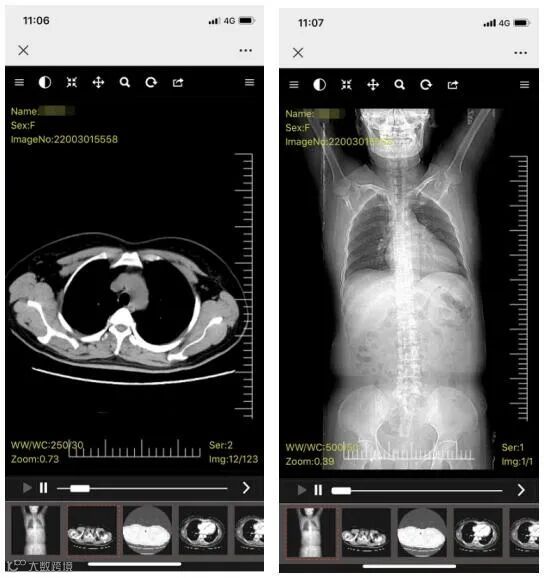

博为“云胶片”与实体胶片一样,承担着向患者告知影像检查结果的重要职责,通过二维码或链接,即可不限次数的浏览DICOM格式影像与报告,还可以通过调节清晰度与对比度,对胶片进行窗宽窗位观察、组织重建等专业处理,在手机、电脑端查看来自不同医院患者的检查结果,对于推动医疗机构之间检查结果互认意义重大,也为转诊、远程会诊提供便利。